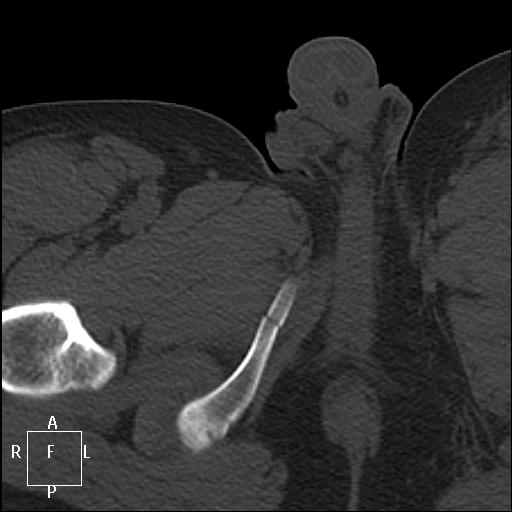

КТ. ДТП. Политравма.

Авария 14 марта, подробностей не знаю. Мужчина 30 лет, сегодня доставлен из другой районной больницы.

1.Красиво...показательно, особенно центральный оскольчастый переломо-вывих бедра.

2. На рутинных рентгенограммах точно были бы пропуски